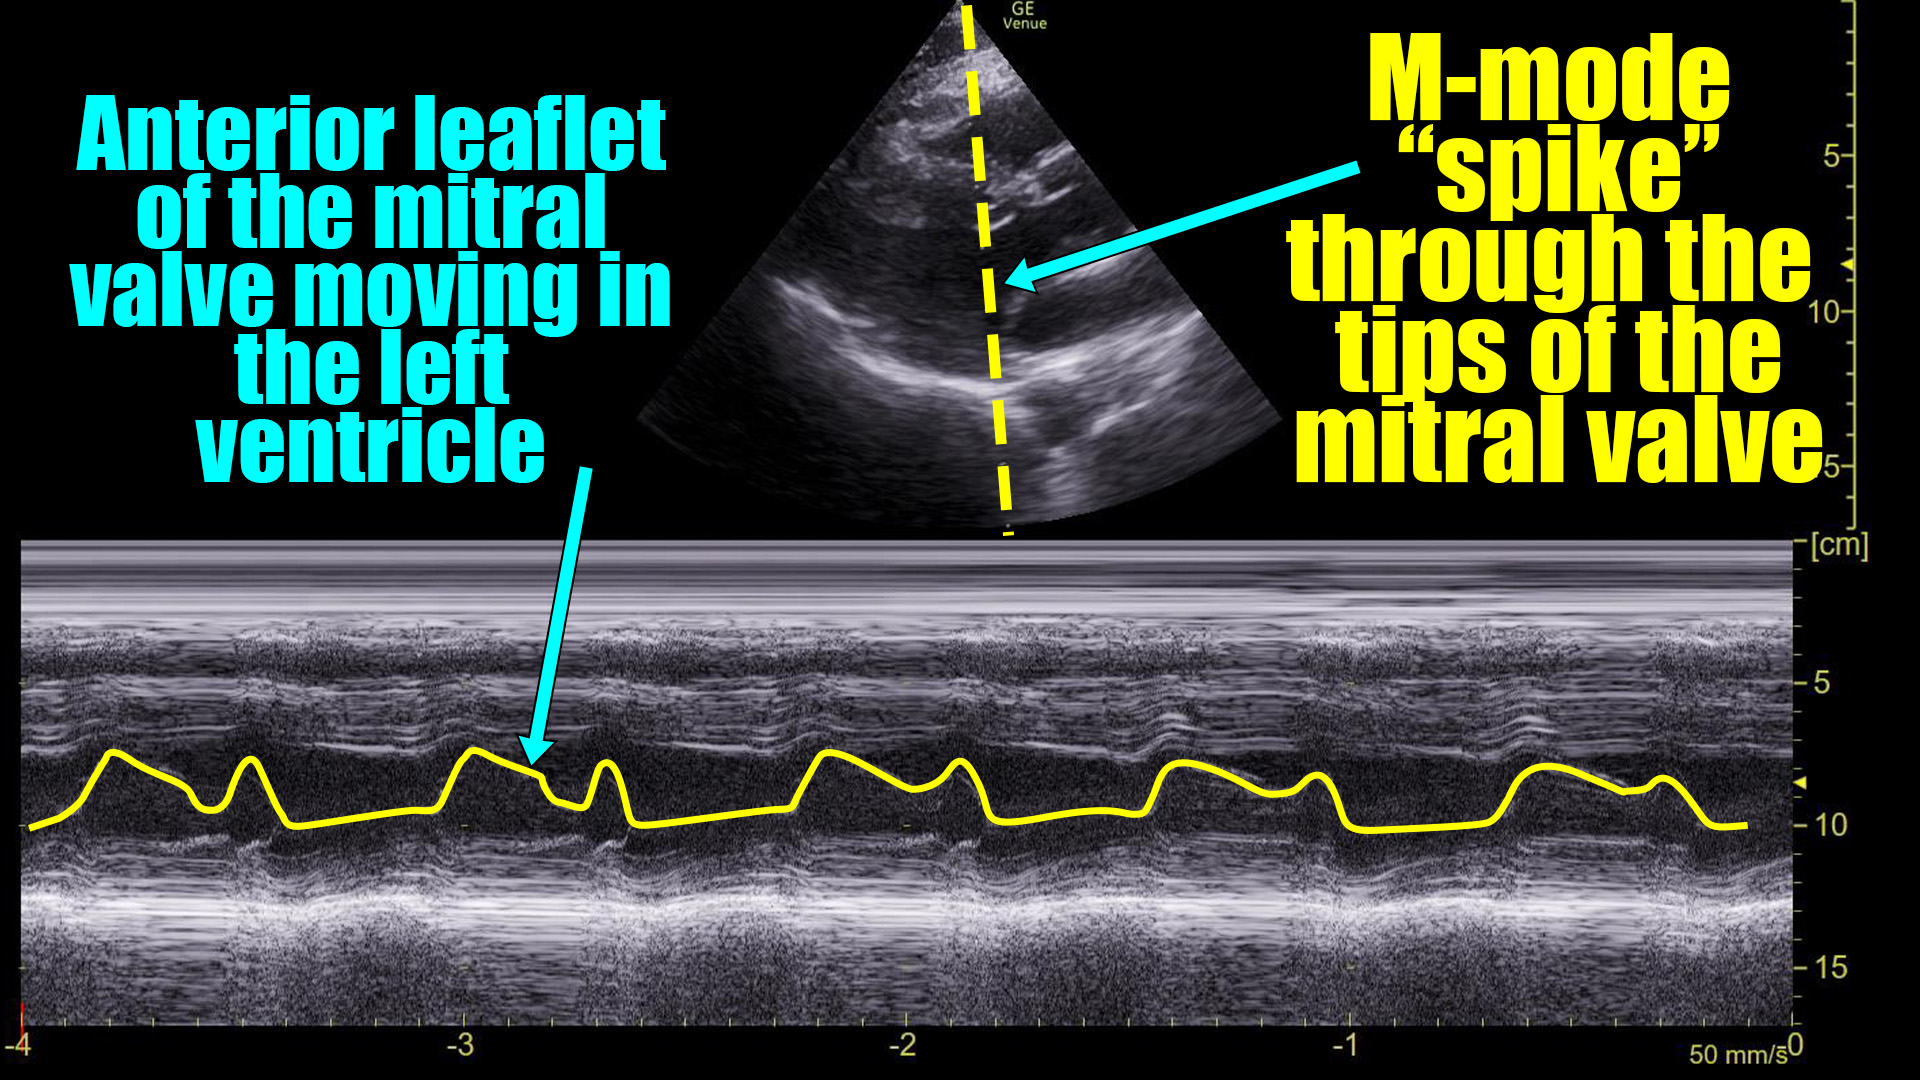

Here it is with the area of interest highlighted.

What we are looking at here is the movement of the mitral valve within the left ventricle – specifically what is highlighted in yellow is the movement of the anterior leaflet of the mitral valve. (Recall that it has two leaflets: anterior and posterior.)

You can see that the leaflet flaps once per cardiac contraction. That, however, is ABNORMAL!

There are no A-waves.

This tells us that the atria are not contracting in an organized, functional way because the mitral valve is only flapping once during each heart beat.

This cannot be a sinus rhythm. However, it does not necessarily identify what the arrhythmia is. Atrial fibrillation would certainly look like this, although it would probably not be this regular. Atrial flutter with 2:1 block would look like this**. “SVT” would look this way as well as would ventricular tachycardia. The point is that the absence of A-waves at the mitral valve rules out normal atrial contractions, but does not, by itself, define a particular arrhythmia.